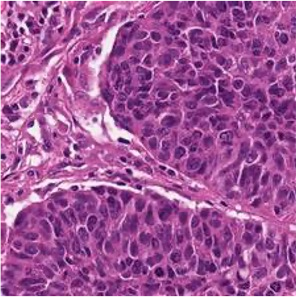

Multiple instance learning (MIL) is a powerful approach to classify whole slide images (WSIs) for diagnostic pathology. A fundamental challenge of MIL on WSI classification is to discover the \textit{critical instances} that trigger the bag label. However, previous methods are primarily designed under the independent and identical distribution hypothesis (\textit{i.i.d}), ignoring either the correlations between instances or heterogeneity of tumours. In this paper, we propose a novel multiplex-detection-based multiple instance learning (MDMIL) to tackle the issues above. Specifically, MDMIL is constructed by the internal query generation module (IQGM) and the multiplex detection module (MDM) and assisted by the memory-based contrastive loss during training. Firstly, IQGM gives the probability of instances and generates the internal query (IQ) for the subsequent MDM by aggregating highly reliable features after the distribution analysis. Secondly, the multiplex-detection cross-attention (MDCA) and multi-head self-attention (MHSA) in MDM cooperate to generate the final representations for the WSI. In this process, the IQ and trainable variational query (VQ) successfully build up the connections between instances and significantly improve the model's robustness toward heterogeneous tumours. At last, to further enforce constraints in the feature space and stabilize the training process, we adopt a memory-based contrastive loss, which is practicable for WSI classification even with a single sample as input in each iteration. We conduct experiments on three computational pathology datasets, e.g., CAMELYON16, TCGA-NSCLC, and TCGA-RCC datasets. The superior accuracy and AUC demonstrate the superiority of our proposed MDMIL over other state-of-the-art methods.